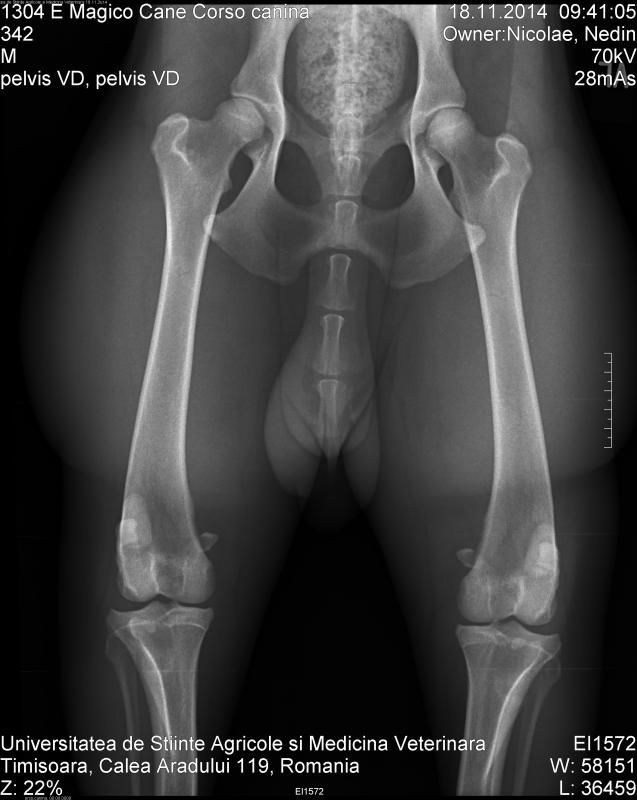

En wat vinden jullie van de heupfoto's?

Heb ze ook al doorgestuurd naar Maarten Kapen, maar ben ook benieuwd naar jullie mening